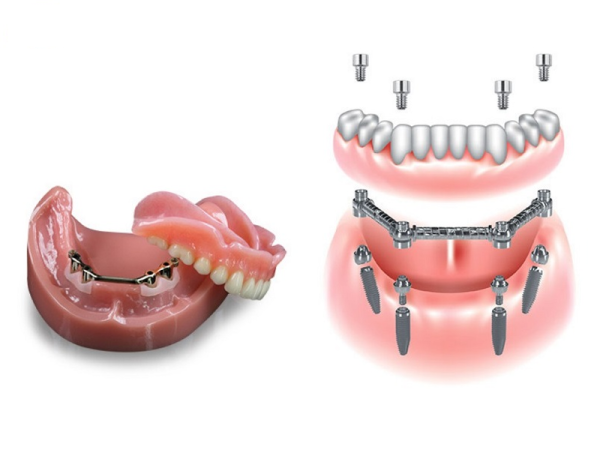

Hàm phủ/ghép trên implant (kết hợp implant + hàm giả)

Hàm phủ/ghép trên implant là giải pháp kết hợp giữa hàm giả tháo lắp và trụ Implant, giúp tăng độ ổn định, cải thiện khả năng ăn nhai so với hàm tháo lắp thông thường. Hàm giả được gắn cố định một phần trên 2-4 trụ Implant đặt trong xương hàm, giúp hàm bám chắc hơn, không bị trượt khi ăn nhai hay nói chuyện.

Ưu điểm:

- Cải thiện đáng kể lực nhai, mang lại cảm giác chắc chắn, tự nhiên.

- Dễ tháo rời để vệ sinh, bảo dưỡng.

- Giúp giảm tiêu xương hàm so với hàm tháo lắp thông thường.

Hạn chế:

- Chi phí cao hơn so với hàm giả truyền thống.

- Cần thời gian chờ tích hợp xương sau khi đặt trụ Implant.

Phương pháp này thích hợp cho những cô chú anh chị muốn phục hồi cố định tương đối, có xương hàm đủ điều kiện cấy ghép và mong muốn tăng hiệu quả ăn nhai, giao tiếp tự nhiên hơn.